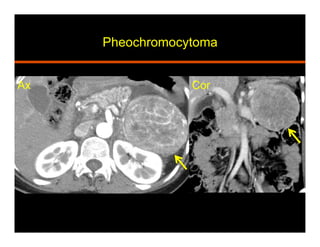

Pheochromocytoma

•  Arises from Chromaffin cells in adrenal medulla

•  Stores and releases catecholamines

•  Elevated serum / 24 hr urine metanephrines

•  Hypertension, palpitations, perspiration and headache

•  10% are: bilateral, extra adrenal (paragangliomas), occur

in children, and malignant (local invasion and mets)

•  Association with syndromes: MEN, NF 1, Von Hippel

Lindau, Tuberous sclerosis, Sturge-Weber

•  CT: homogeneous, well defined, soft tissue attenuation,

avid enhancement with delayed retention

•  MR: T2 bright (light bulb)

•  Take up I123 MIBG, In111 pentetreotide, and F18 FDG

•  Surgical resection

•  Pathology: yellow / tan, hemorrhage, cystic change,

central necrosis, myxoid degeneration. Nest of cells

(zellballen), Salt and pepper chromatin

Ax Cor